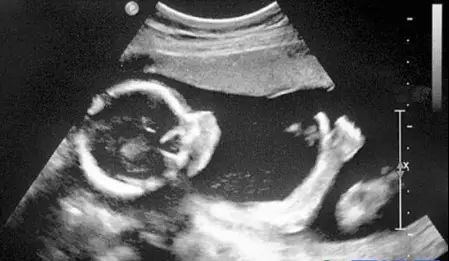

B超的原理是用超声波穿透人体,当声波遇到人体组织时会产生反射波,通过计算反射波成像。就像挑西瓜一样,边敲边看显示病灶情况。